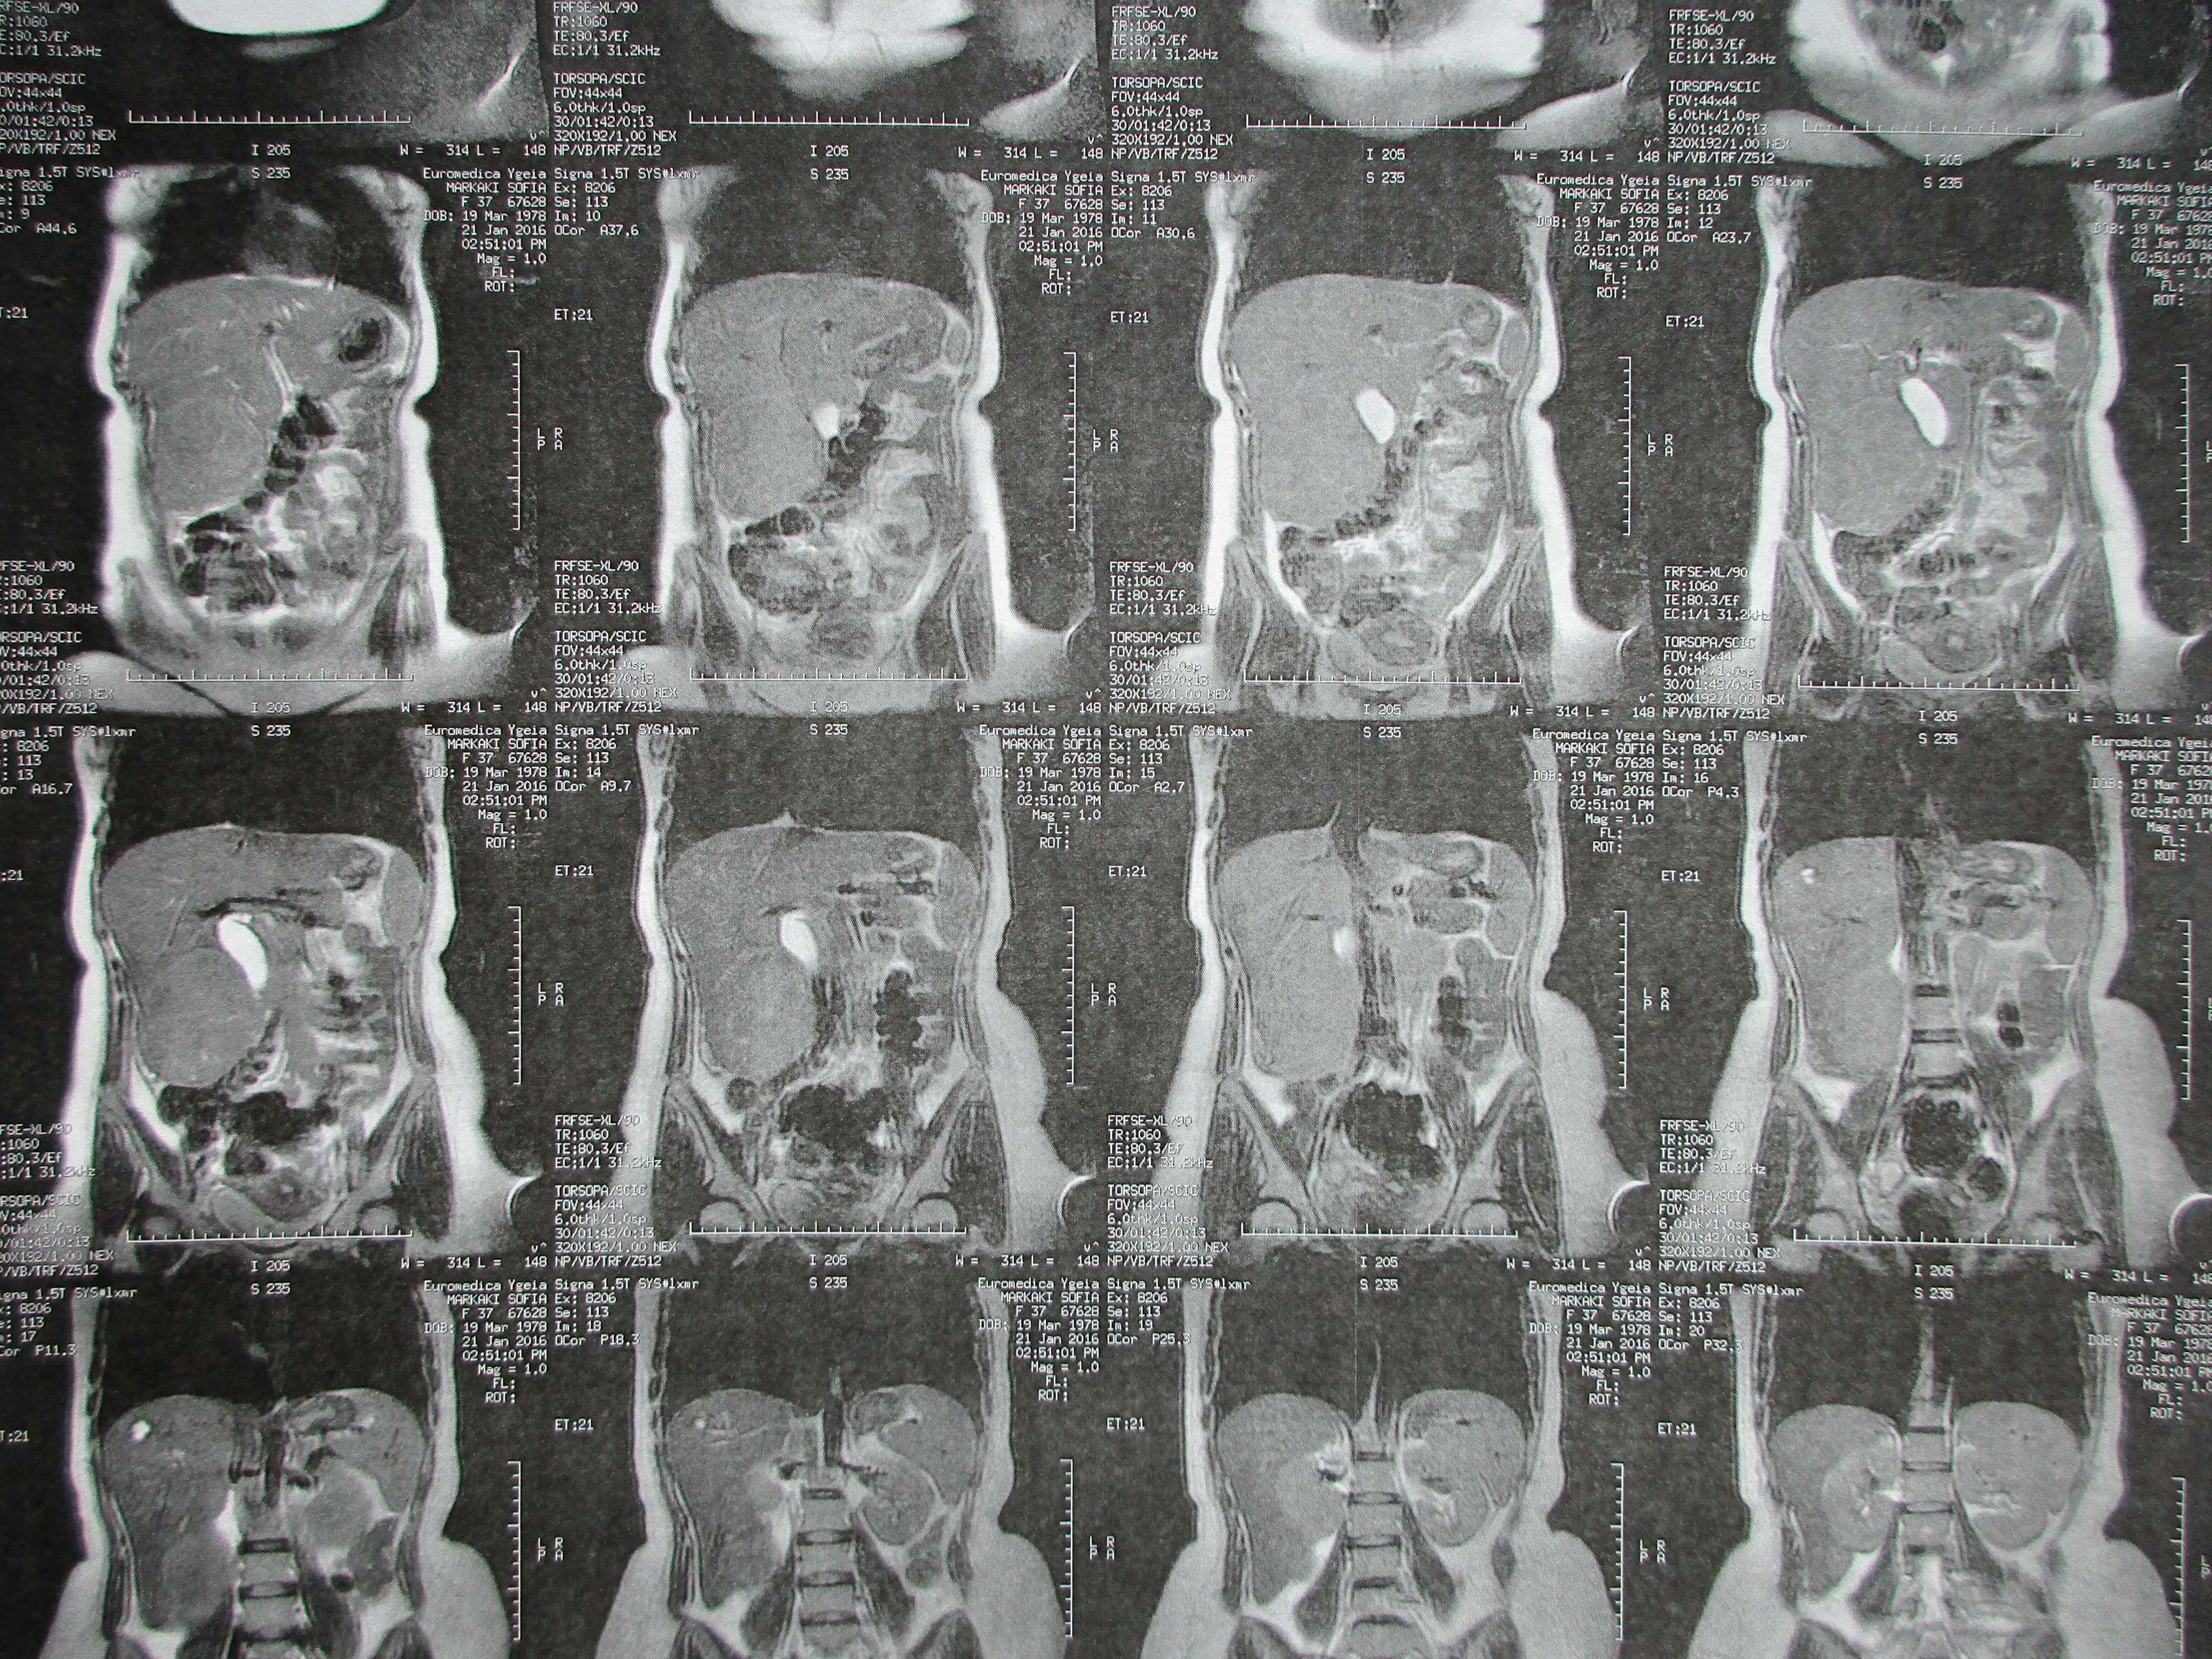

Μετεγχειρητική απεικόνιση ειλεορθικής αναστόμωσης (τροποποιημένη Duhamel). Εμφανής η αναστόμωση του τερματικού ειλεού στο πρόσθιο τοίχωμα του εναπομένοντος κολοβώματος ορθού (Ευγενική παραχώρηση Dr. V. Penopoulos)